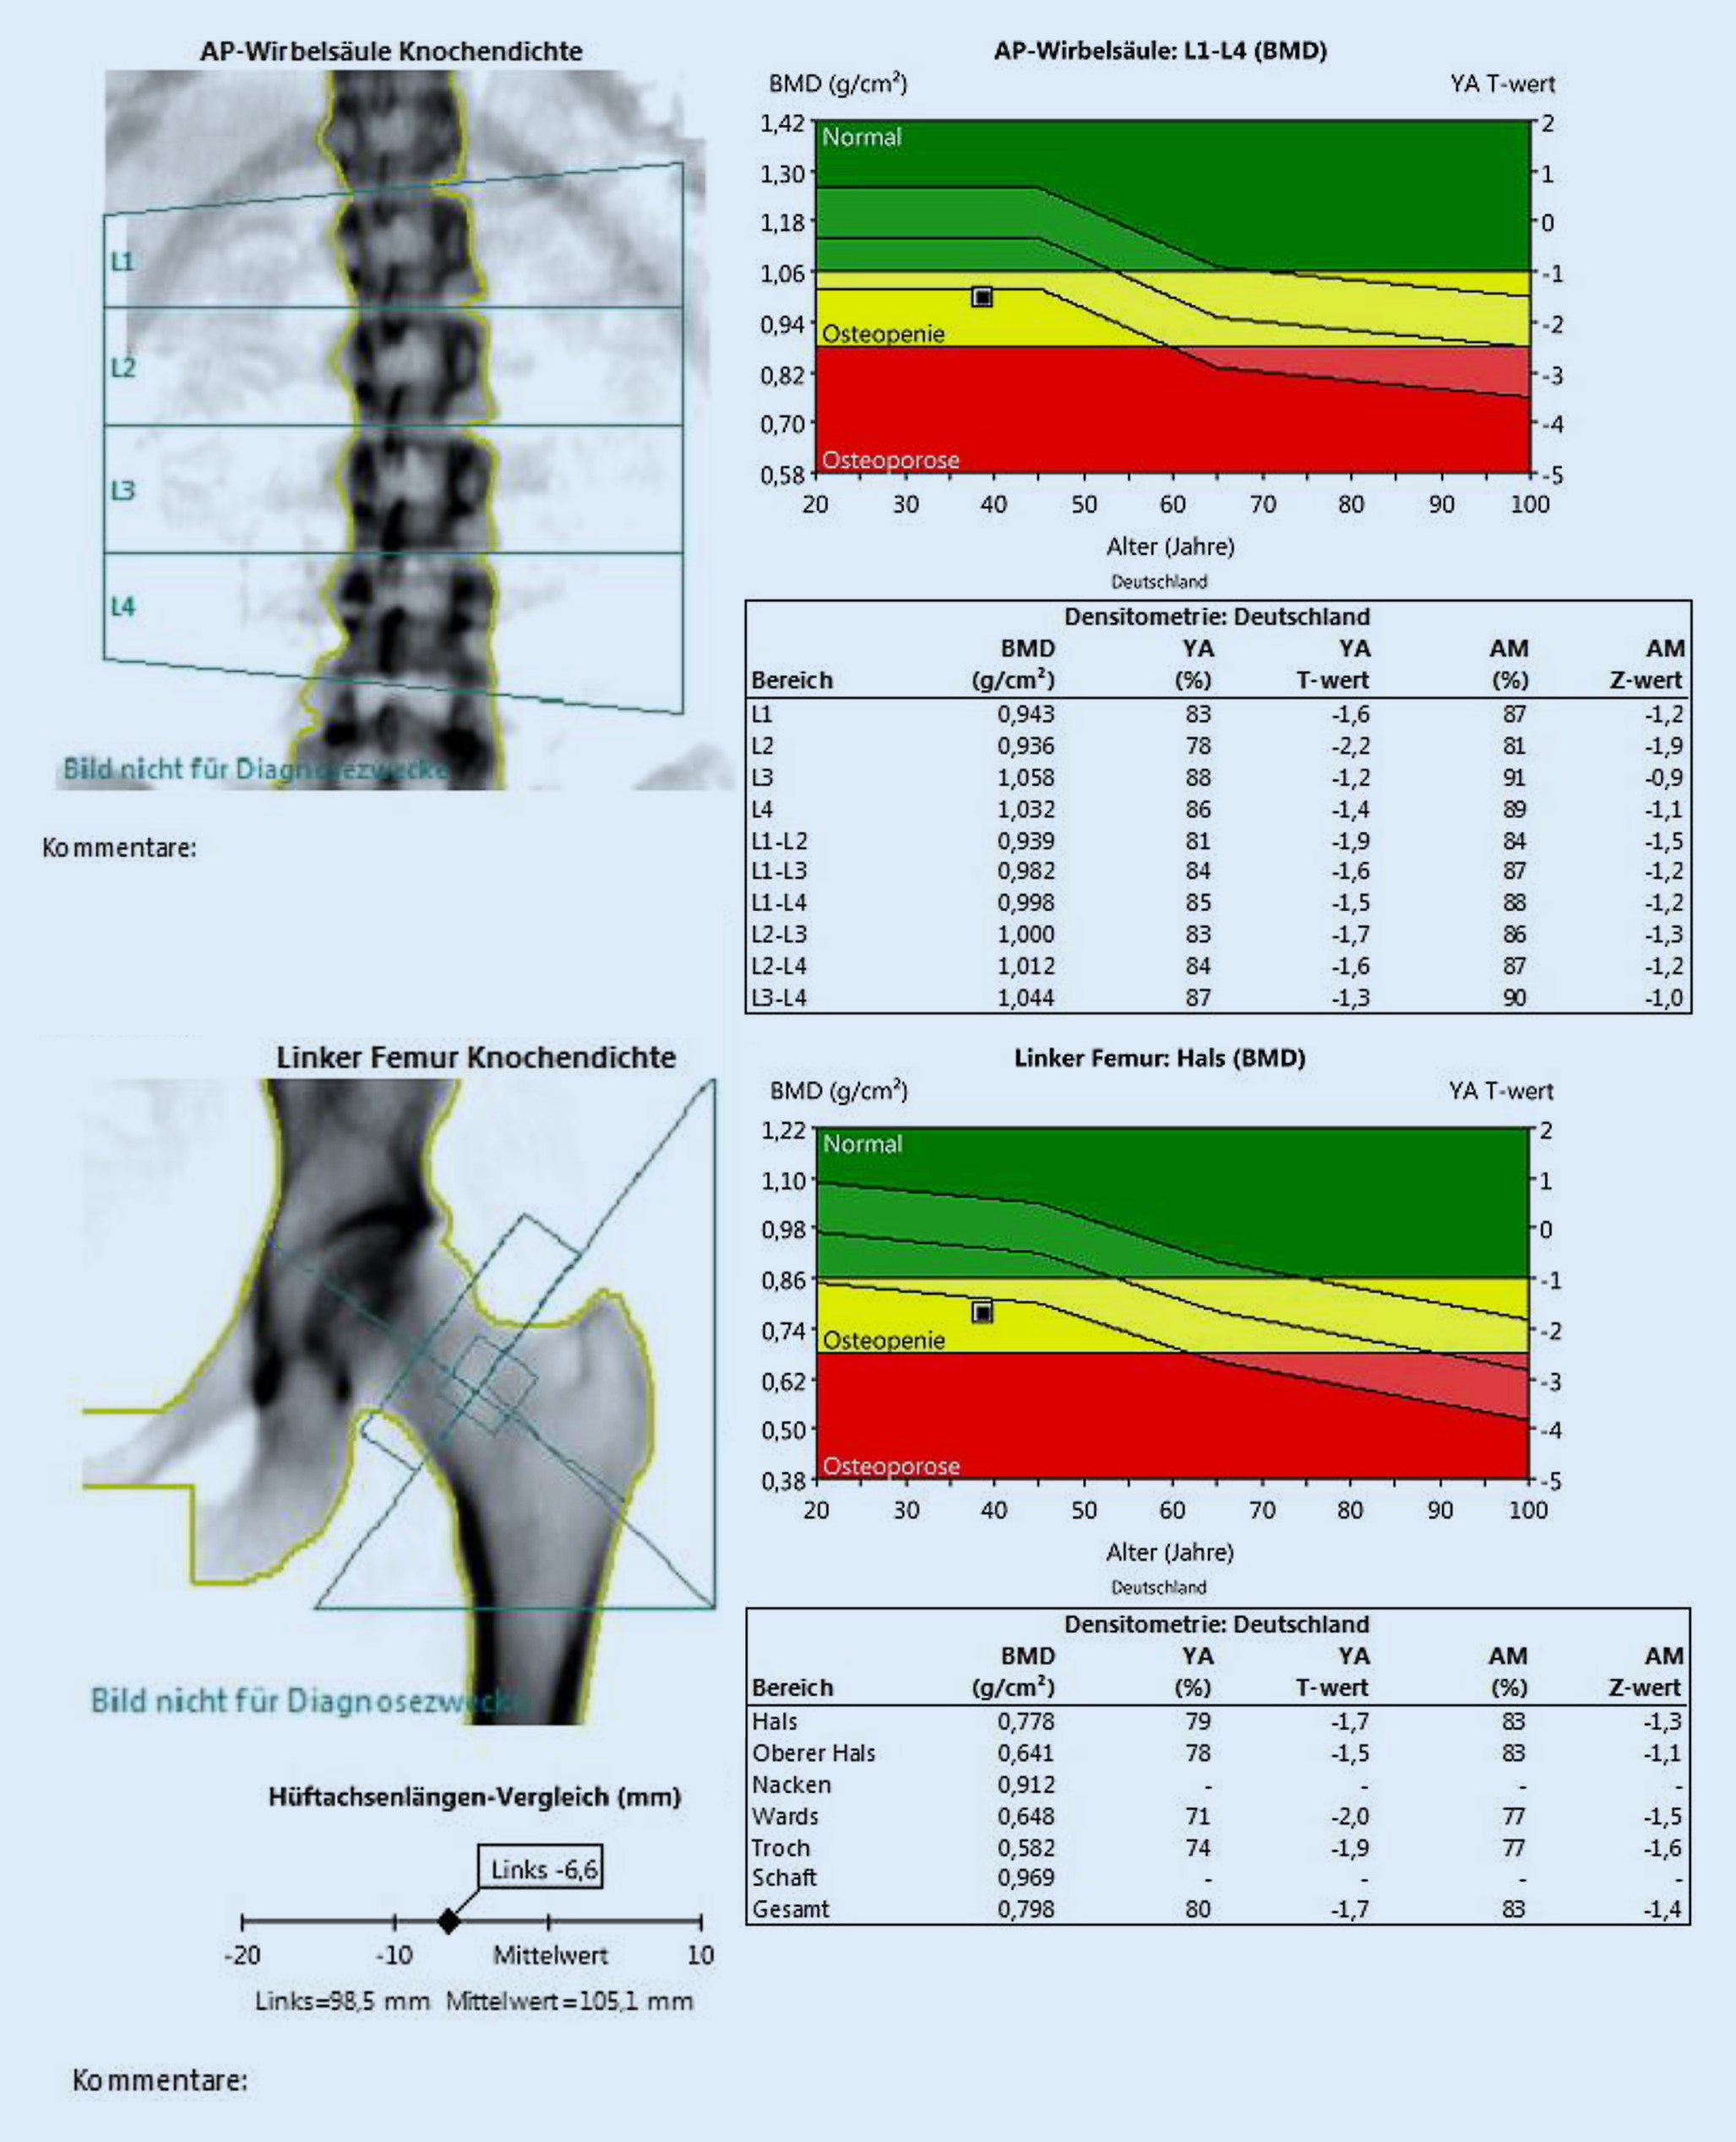

The shaded areas represents the changes of bmd with age. A baseline bone density test is recommended by the national osteoporosis foundation and other professional groups for all women 65 years old and based on the study results, women without risk factors should ask for a bone density test as soon as possible after age 65 and then discuss the. A bone density scan can detect thinning bones at an early stage.